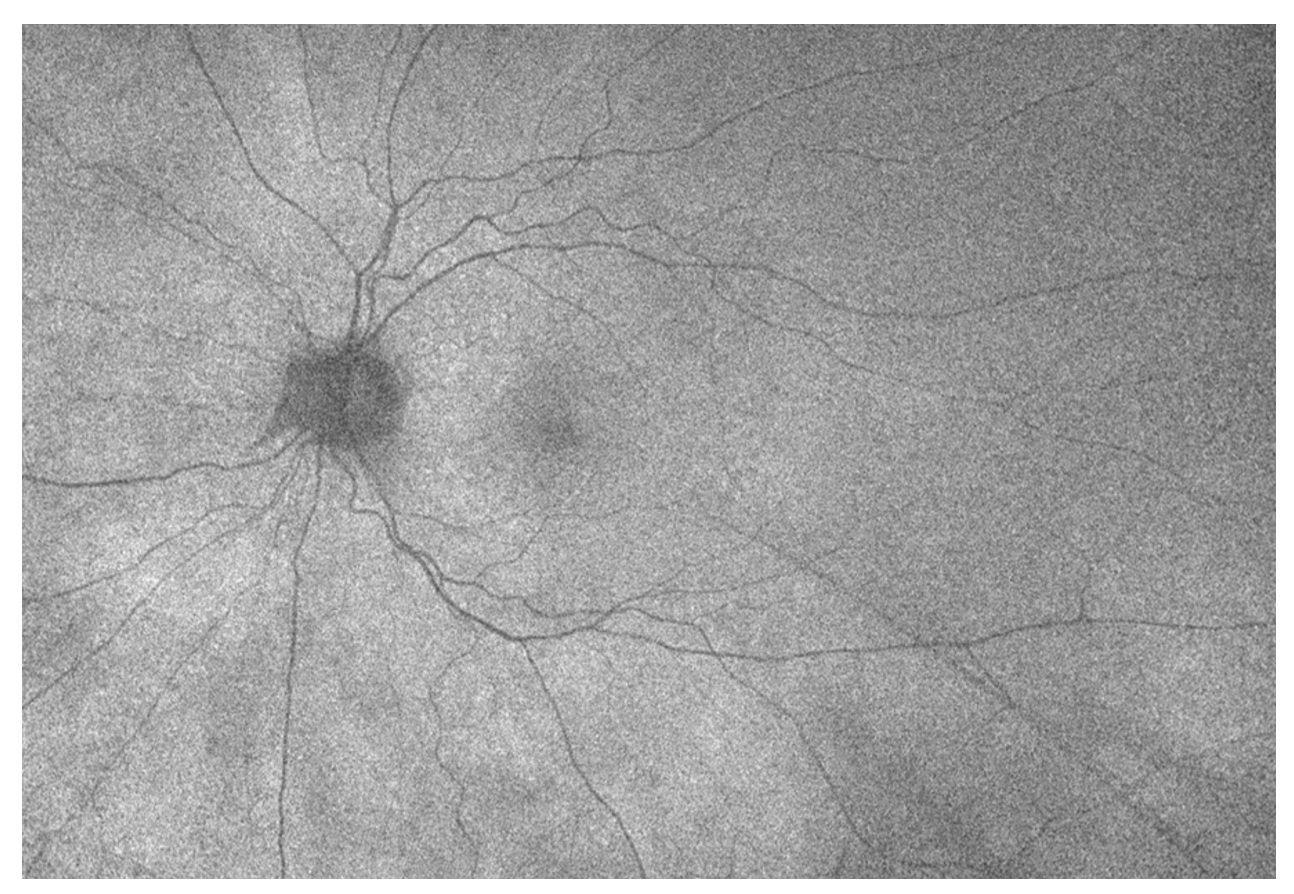

A 77-year-old female with history of cataracts, HTN, HLD, DM2, and aortic stenosis presents for new spots in the left eye. She denies flashes of light, photophobia and new floaters. Visual acuity is 20/40 OU (uncorrected) and anterior segment exam demonstrates trace nuclear sclerosis OU without vitreous cell in either eye. What is the diagnosis? What other diagnoses should be considered? How would you manage this patient?